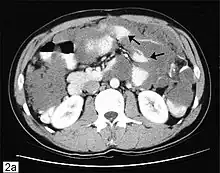

Ovarian adenocarcinoma deposit in the mesentery of the small bowel

Metastasis in ovarian cancer is very common in the abdomen and occurs via exfoliation, where cancer cells burst through the ovarian capsule and are able to move freely throughout the peritoneal cavity. Ovarian cancer metastases usually grow on the surface of organs rather than the inside; they are also common on the omentum and the peritoneal lining. Cancer cells can also travel through the lymphatic system and metastasize to lymph nodes connected to the ovaries via blood vessels; i.e. the lymph nodes along the infundibulopelvic ligament, the broad ligament, and the round ligament. The most commonly affected groups include the paraaortic, hypogastric, external iliac, obturator, and inguinal lymph nodes. Usually, ovarian cancer does not metastasize to the liver, lung, brain, or kidneys unless it is a recurrent disease; this differentiates ovarian cancer from many other forms of cancer.[29]

In advanced cancers, where complete removal is not an option, as much tumor as possible is removed in a procedure called debulking surgery. This surgery is not always successful, and is less likely to be successful in women with extensive metastases in the peritoneum, stage- IV disease, cancer in the transverse fissure of the liver, mesentery, or diaphragm, and large areas of ascites. Debulking surgery has usually only been done once[28] but a recent study has shown a longer overall survival in recurrent ovarian cancer when surgery combined with chemotherapy was performed compared to treatment with chemotherapy alone.[95] Computed tomography (abdominal CT) is often used to assess if primary debulking surgery is possible, but low certainty evidence also suggests fluorodeoxyglucose‐18 (FDG) PET/CT and MRI may be useful as an addition for assessing macroscopic incomplete debulking.[96] More complete debulking is associated with better outcomes: women with no macroscopic evidence of disease after debulking have a median survival of 39 months, as opposed to 17 months with less complete surgery.[26] By removing metastases, many cells that are resistant to chemotherapy are removed, and any clumps of cells that have died are also removed. This allows chemotherapy to better reach the remaining cancer cells, which are more likely to be fast-growing and therefore chemosensitive.[29]